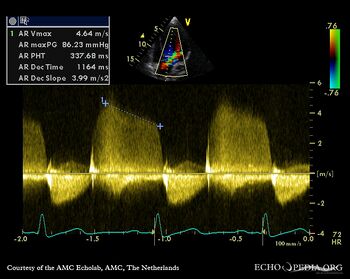

Doppler auscultation It is The Doppler auscultation presented a sensitivity of 84% for the detection of aortic regurgitations while classic stethoscope auscultation presented a sensitivity of 58%. Abdominal: Digestive: Liver span; Rectal; Murphy's sign; Bowel sounds; ... Read Article